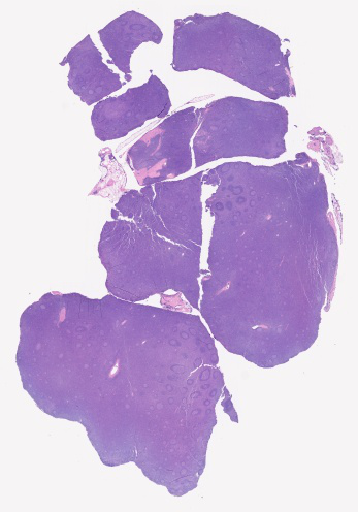

Pathology Image Library

ARUP Laboratories®